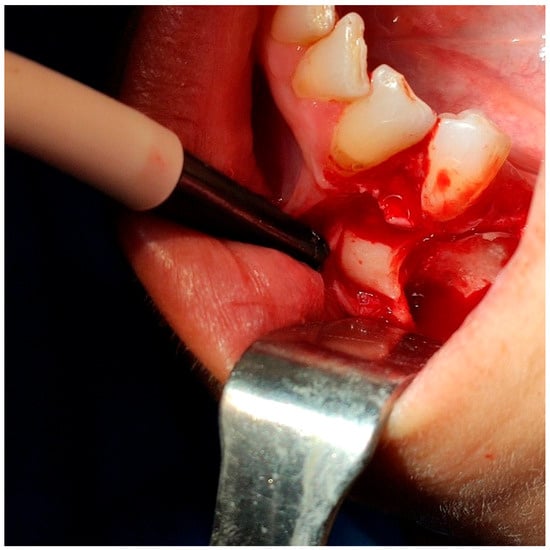

2.2. Surgical Intervention